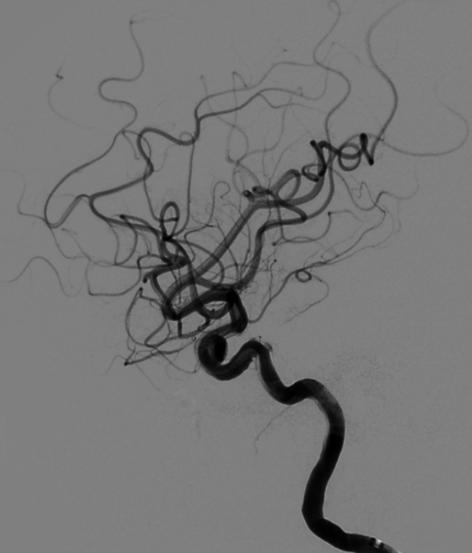

随访结果:

术后6个月复查动脉瘤完全闭塞,局部血管重建。